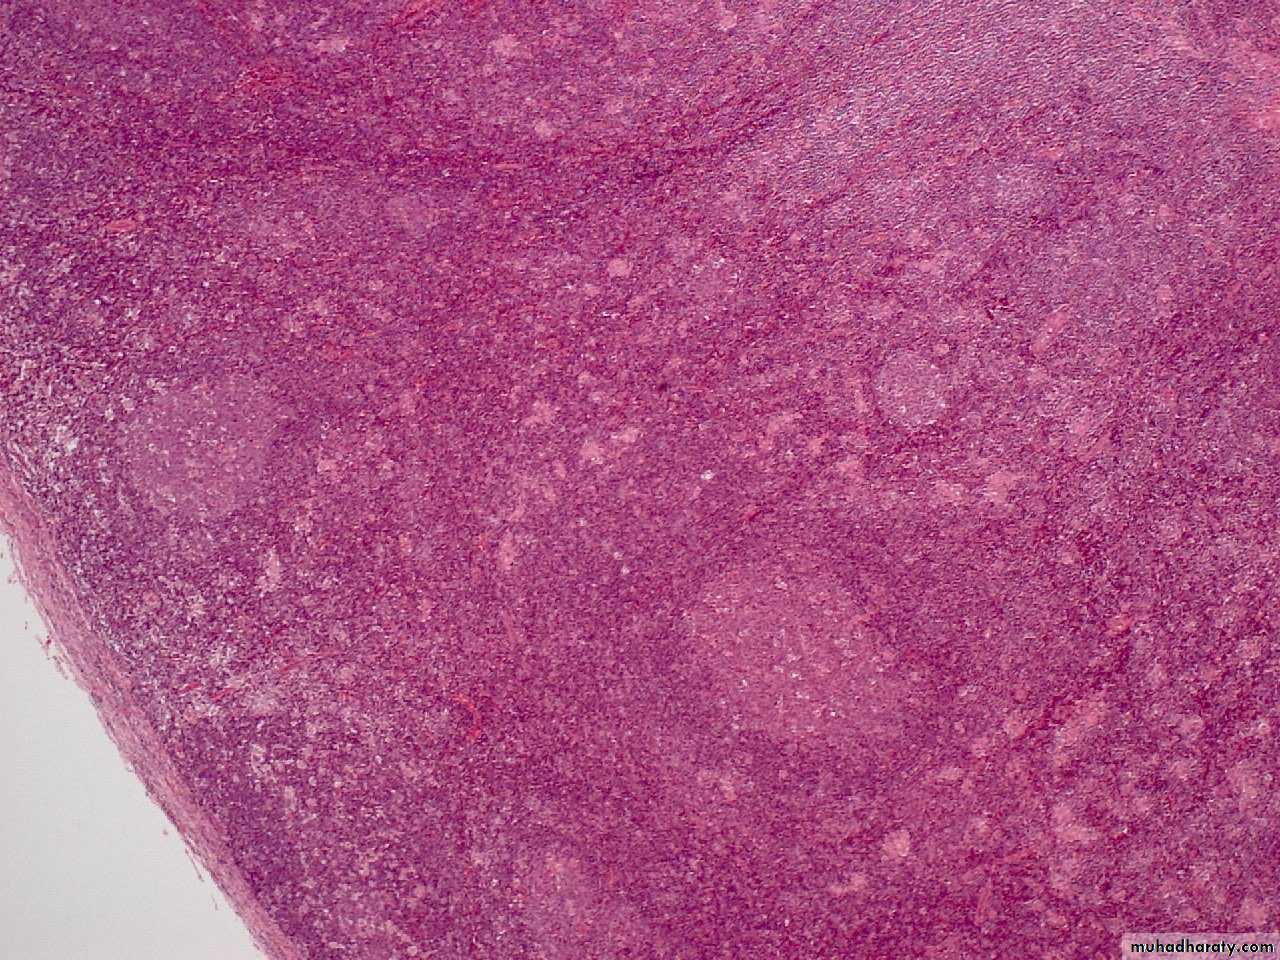

NSCHD

M. 39Y. PARA AORTIC, MESENTRIC LYMPHADEOPATHY,ANAEMIA,LETHARGY, NODE BIOPSYHodgkin's disease, nodular sclerosis type, lacunar cell HP mic

large cells with a surrounding prominent clear space, an artefact of formalin fixation. These are the lacunar cells characteristic for the nodular sclerosis type of Hodgkin's disease.M. 39Y. PARA AORTIC, MESENTRIC LYMPHADEOPATHY,ANAEMIA,LETHARGY, NODE BIOPSY